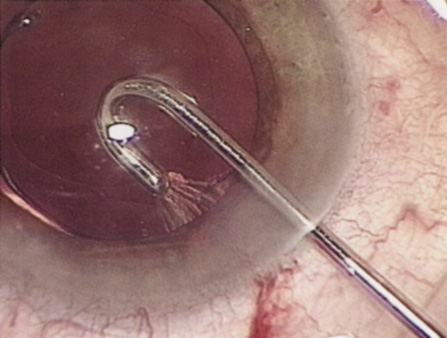

Hydrodissection can be performed after the surgeon has successfully completed capsulorrhexis.97 If the capsulorrhexis is not intact, fluid forced around the interior of the capsule may cause the bag to splay open. With capsulorrhexis, hydrodissection is a safe and extremely useful maneuver. Hydrodissection can be thought of as two maneuvers: hydrodelineation and cortical cleaving hydrodissection. By placing a 27-gauge cannula on a syringe filled with balanced saline solution (BSS), the surgeon can direct fluid beneath the residual anterior capsular rim to create a cleavage plane. Depending on the direction the fluid wave takes, different lamellae of the cataract will be separated. Hydrodelineation is the term used when the cleavage plane separates the adult nucleus from the fetal nucleus or the adult nucleus from the more peripheral epinucleus. Hydrodelineation often results in the characteristic golden ring sign (Fig. 11). Cortical cleavage occurs when the cortex is separated from the capsular bag (Fig. 12). Finding the cortical cleavage plane may be facilitated by gently lifting the capsular margin away from the cortex with the BSS cannula before injecting. Several small bursts of fluid allow the surgeon to monitor progress of the fluid wave. When dealing with a soft nucleus, the authors strive to perform true cortical cleaving hydrodissection. For a hard nucleus, hydrodelineation allows manipulation of less of the nuclear bulk, although the remaining epinuclear shell must be addressed in an additional step. Hydrodelineation is particularly useful if the nucleus is not freely mobile after cortical cleaving hydrodissection.

Fig. 12. Hydrodissection, performed subincisionally with a 27-gauge J-cannula, produces a cleavage plane between the capsule and the cortex. The small blue arrows indicate the advancing fluid wave.